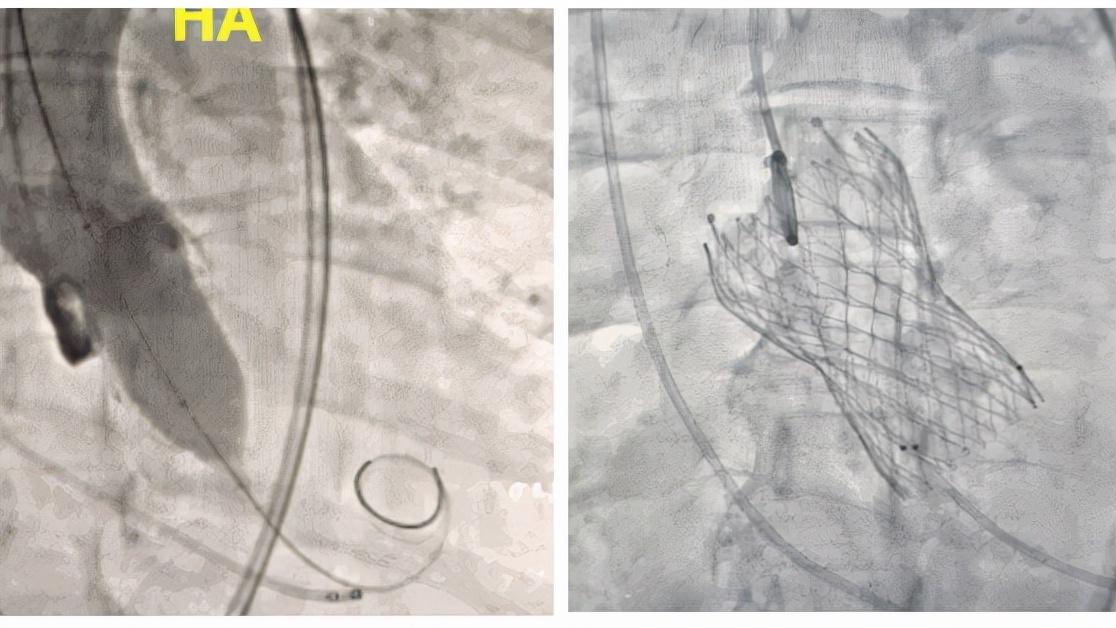

除了进行心脏瓣膜置换手术,近几年瓣膜病介入治疗的方法也越来越受到欢迎,发展速度也和快,尤其对于不能满足手术条件但本身疾病还很严重的人群来说,这是一个很大的福音。